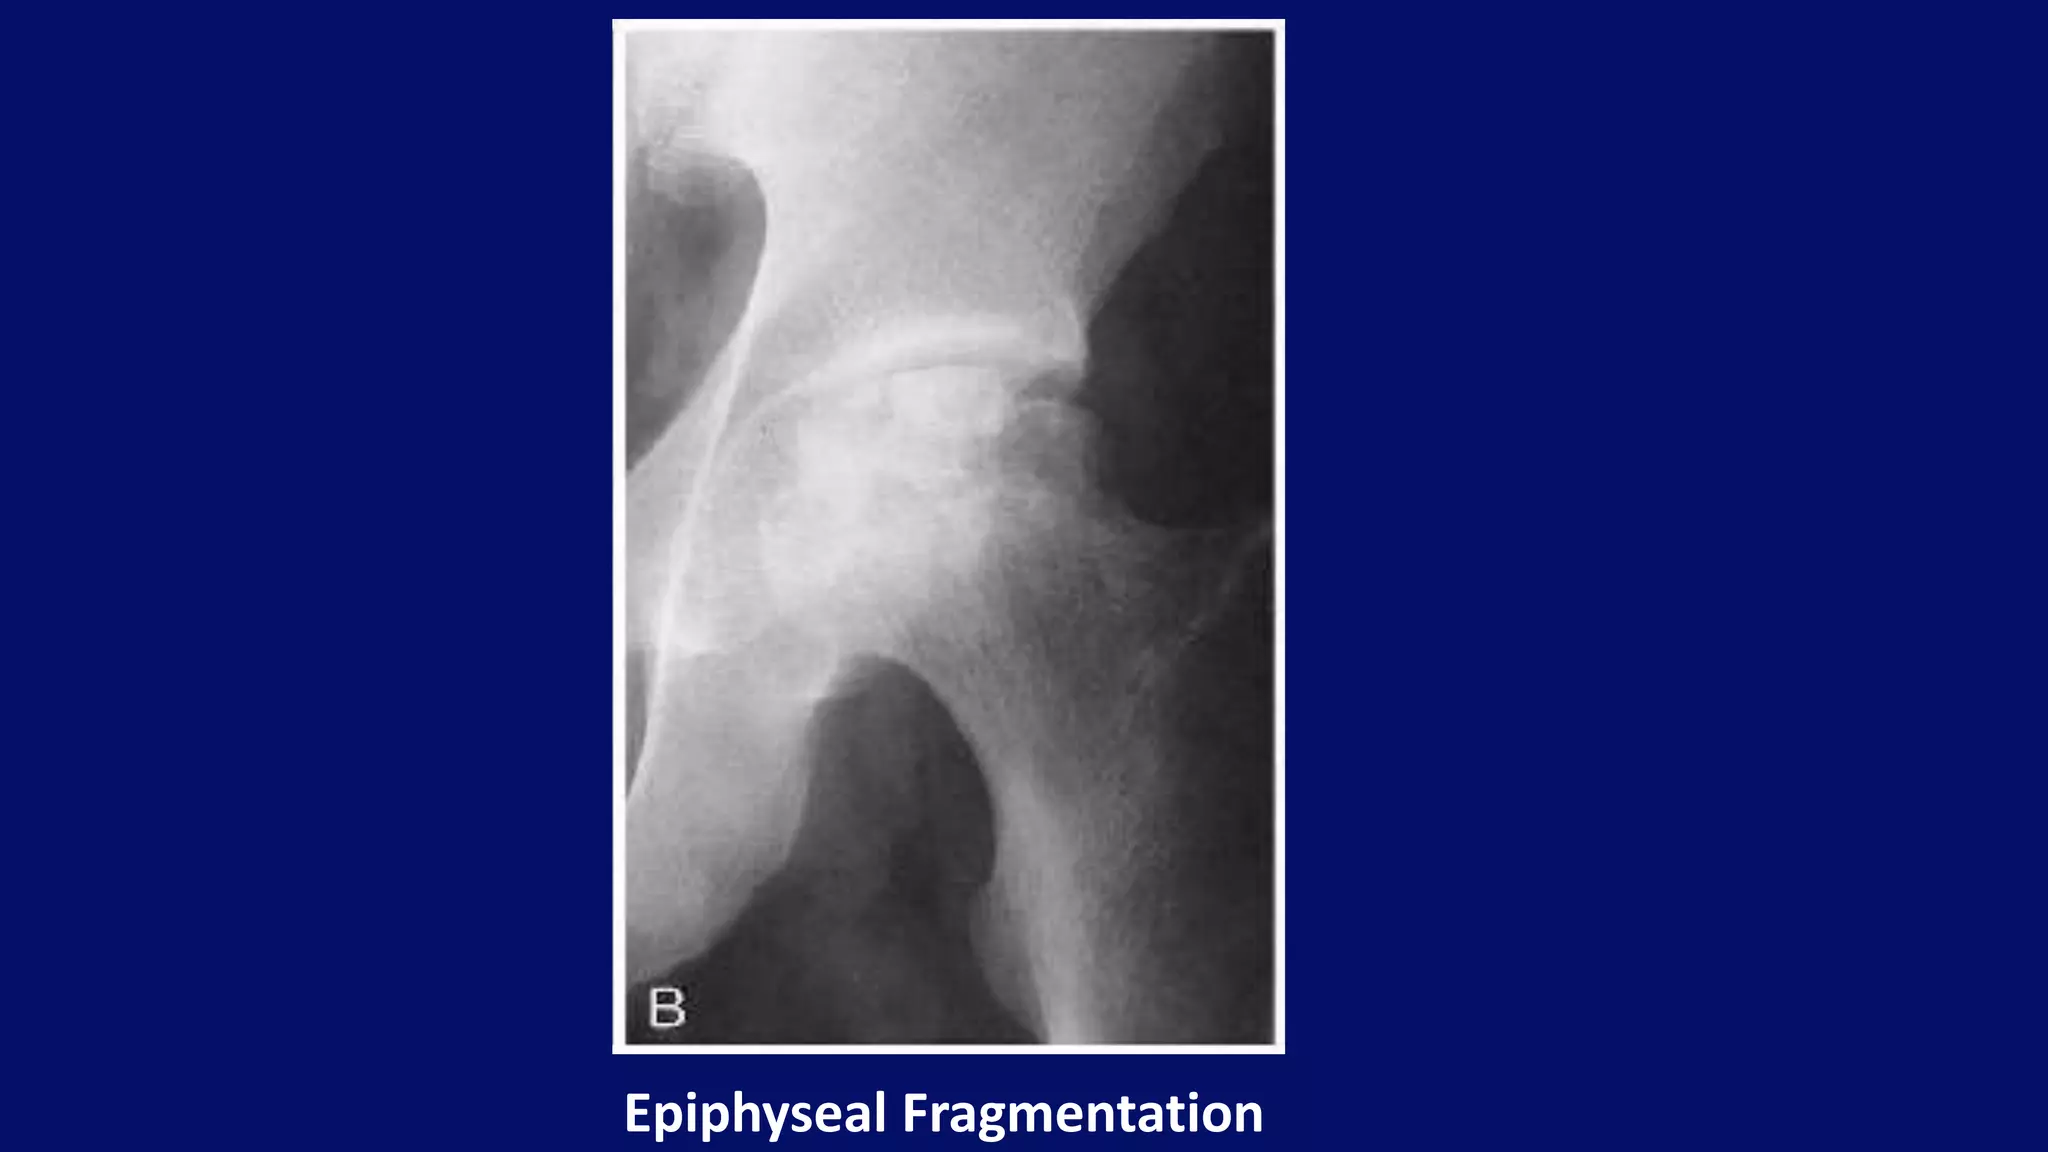

• Collapse of articular cortex

• Fragmentation

• Mottled trabecular pattern

• Sclerosis (Snowcap sign)

• Subchondral cysts

• Crescent sign (Subchondral fracture)

Radiographic features

Epiphyseal Fragmentation